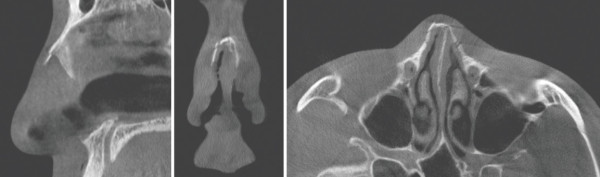

5b20f0b2d5a7f90b24c2bdfd0ae62eeb_1773280340_1782.jpg

수술 전 CT scan. 좌측 안와 주변에 심한 부종이 관찰된다. 주로 좌측 비골골절과 비중격의 안장코 변형을 확인할 수 있다.